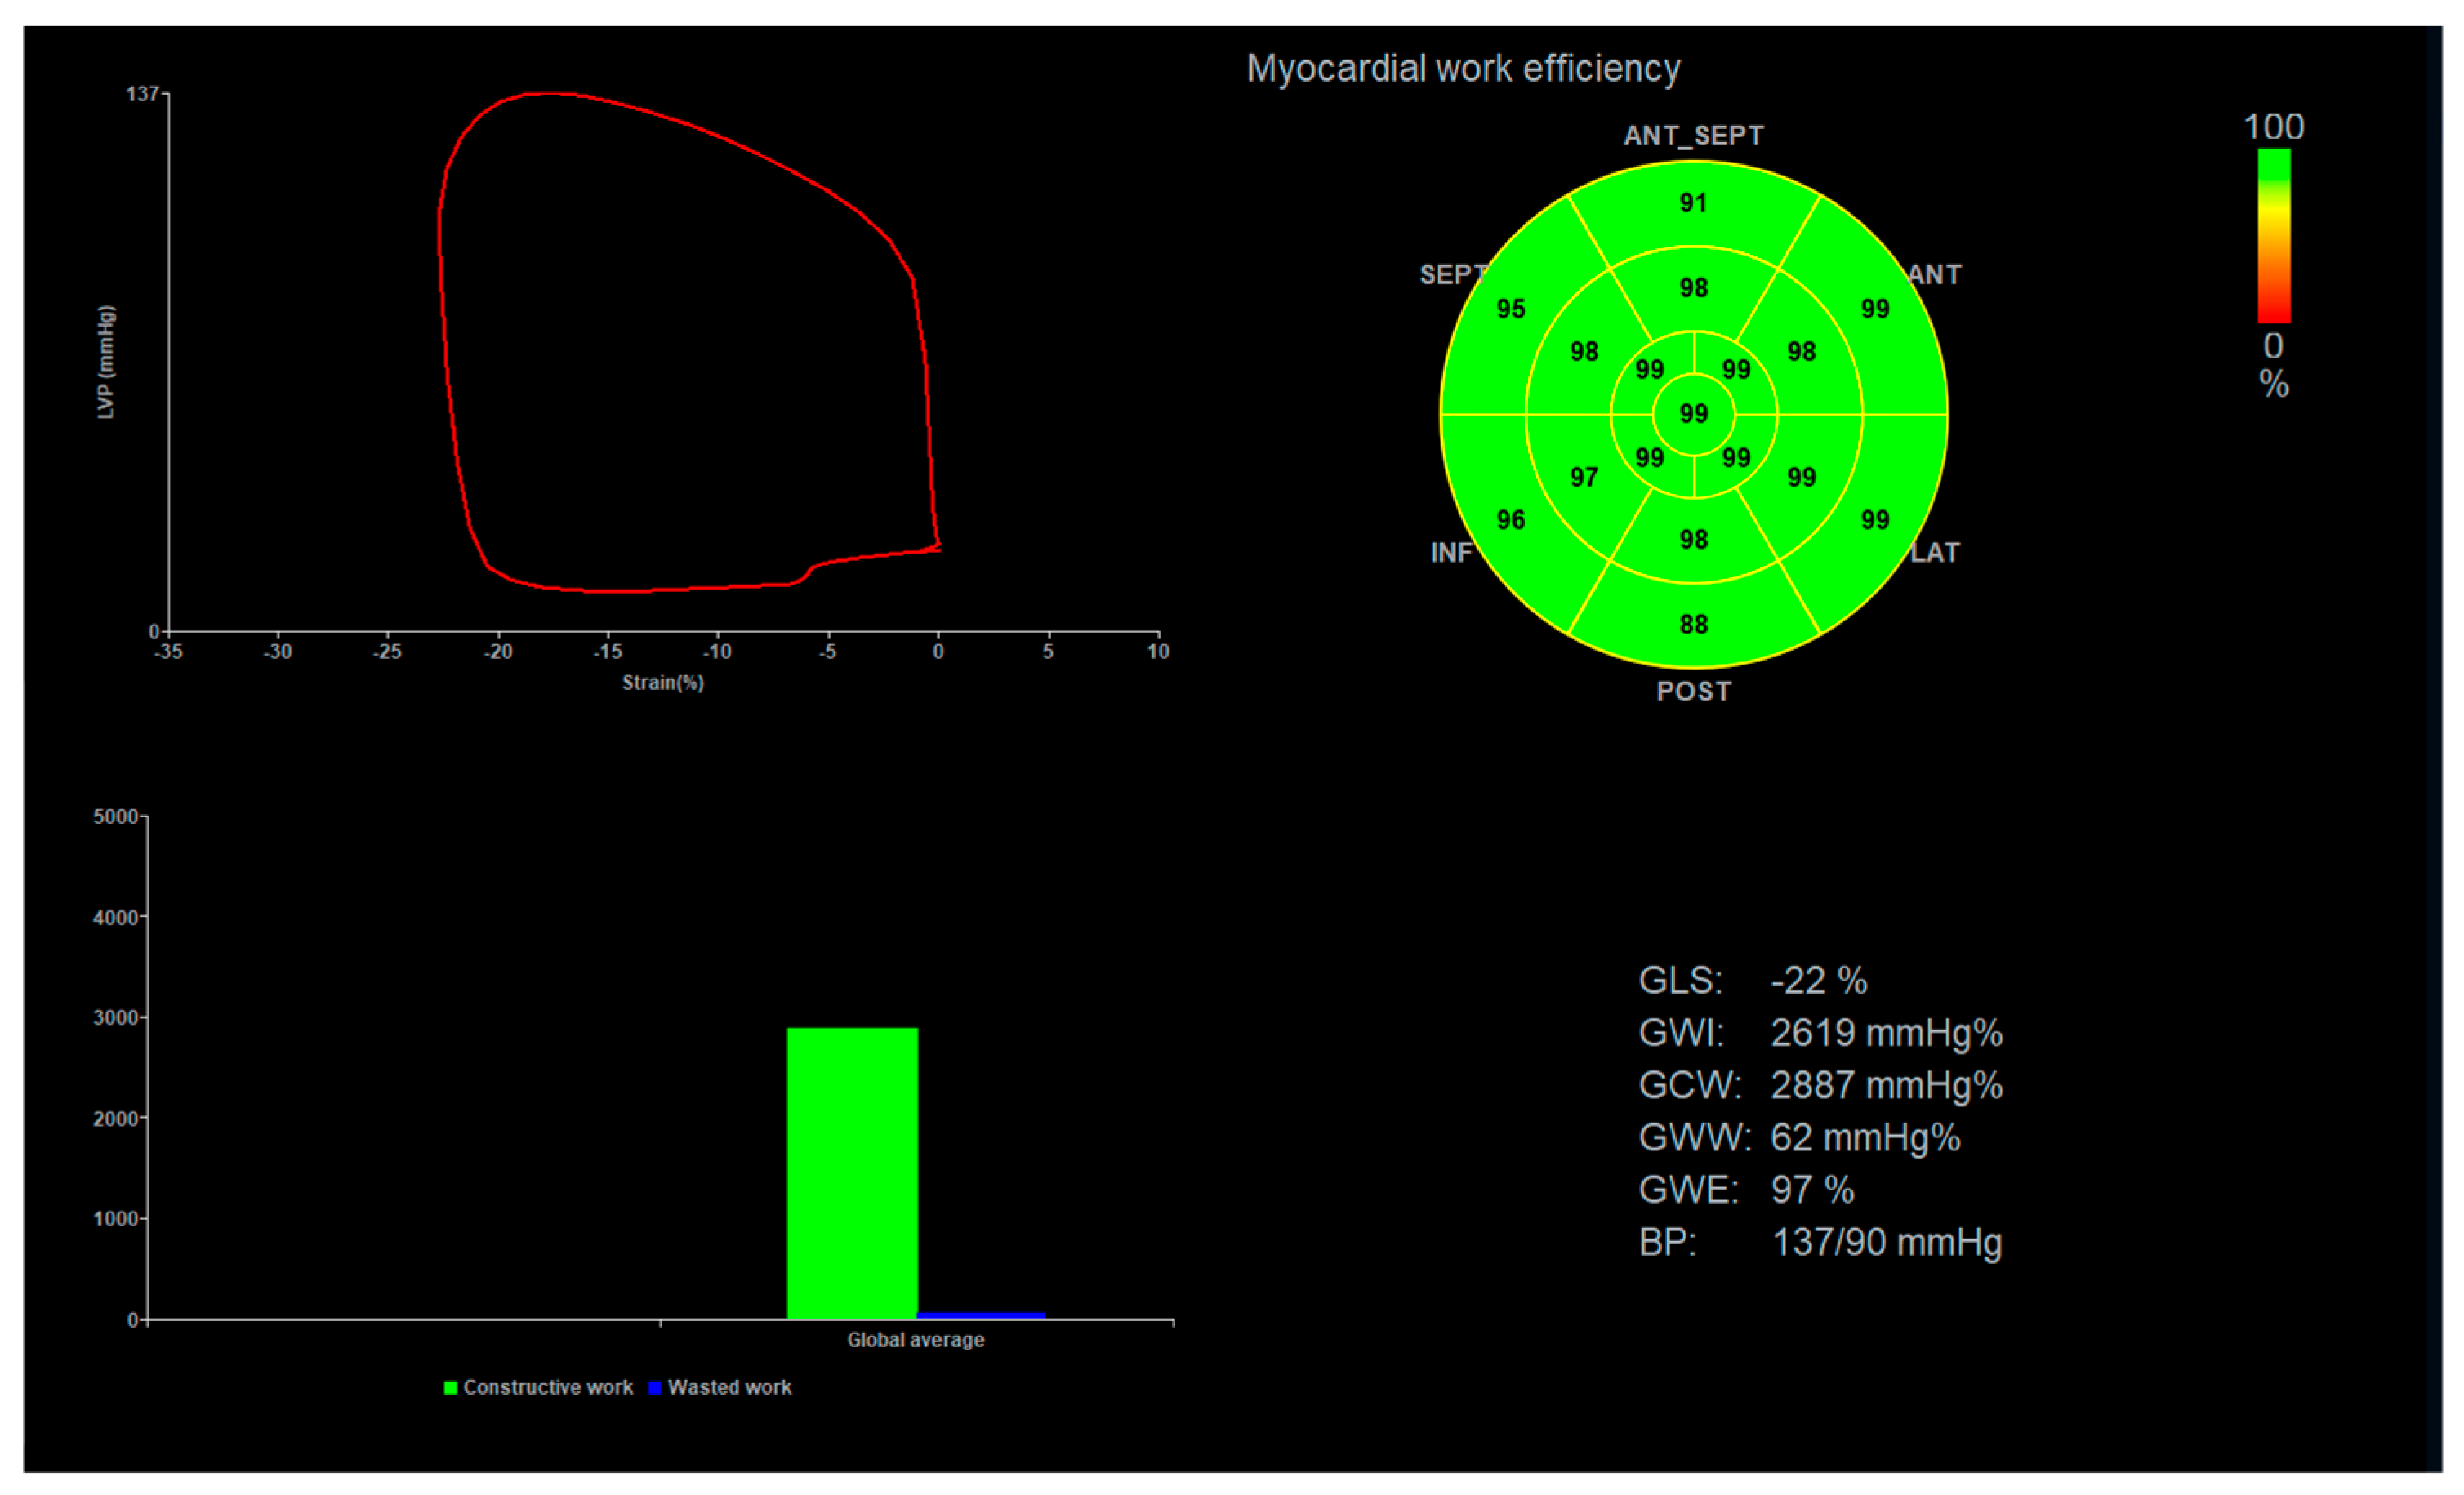

2.2. Global Longitudinal Strain and Myocardial Work Analysis

3.2. Global Longitudinal Strain, Peak Systolic Dispersion, and Myocardial Work Indices

4. Discussion

4.1. Summary of Findings

4.3. Importance of Myocardial Work Indices